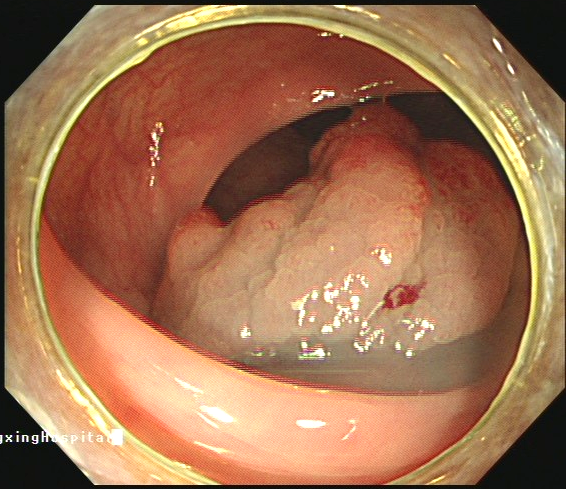

△息肉樣腫物

因病例比較罕見(jiàn),同時(shí)為了保證治療效果和手術(shù)安全,蘇軍凱博士組織科室人員進(jìn)行詳細(xì)的病例討論,反復(fù)研讀CT影像,充分掌握錢叔的消化系統(tǒng)解剖結(jié)構(gòu)的特殊性,并制定了周密可行的治療及手術(shù)方案,決定為其行“內(nèi)鏡下結(jié)腸息肉樣腫物黏膜下層剝離術(shù)(ESD)+結(jié)腸息肉部分切除術(shù)+結(jié)腸息肉氬離子凝固術(shù)(APC)”。

手術(shù)于11月26日上午開(kāi)始,在麻醉醫(yī)生和手術(shù)團(tuán)隊(duì)的密切配合下,蘇軍凱博士親自主刀,最終憑借豐富的臨床經(jīng)驗(yàn)和現(xiàn)場(chǎng)應(yīng)變能力,精準(zhǔn)施術(shù),數(shù)次嘗試后完成全結(jié)腸檢查,切除較大的2枚息肉,行內(nèi)鏡黏膜下剝離術(shù)(ESD)將降結(jié)腸內(nèi)一枚約25mm×30mm的側(cè)向發(fā)育型腫瘤剝離,并分別給予APC充分電凝止血。